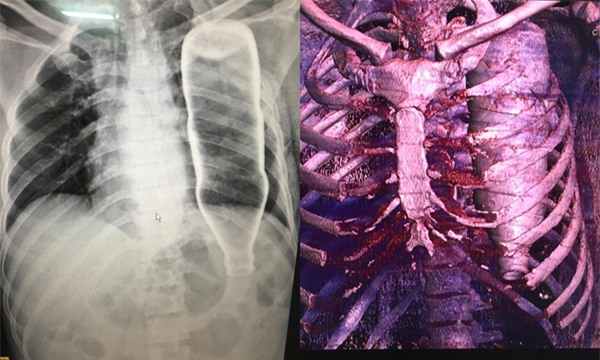

Ngày 28/5, BV Đà Nẵng tiếp nhận một ca cấp cứu vô cùng hy hữu. Bệnh nhân N.H.B (53 tuổi, Quảng Nam) chuyển đến BV trong tình trạng hoảng loạn, khó thở, đau tức ở vùng ngực do bị ngã cầu thang.

Theo lời người nhà, trong lúc vấp ngã, ông B. bị một vật chui vào nhưng không rõ vật gì. Kết quả chụp X-quang và CT khiến tất thảy BS ngỡ ngàng khi nằm trọn trong lồng ngực bệnh nhân là vỏ chai to như như chai nước khoáng, gây gãy 2 xương sườn, lõm xương đòn. Sau phẫu thuật, dị vật được lấy ra là chai đựng nước thuỷ tinh.